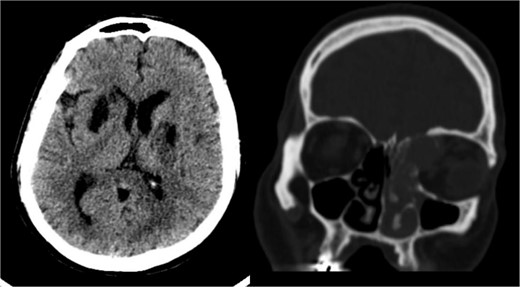

Radiological findings from a high-resolution CT scan (Fig. 1) revealed bilateral basal ganglia hypodense areas suggestive of chronic ischemia and a more lateral hypodense area toward the left basal ganglia indicative of subacute ischemia. A coronal cut showed an iso-dense expansible soft tissue lesion with internal foci of calcifications centered in the anterior aspect of the left ethmoid sinus with protrusion to the left orbital conus, pushing the medial rectus muscle laterally with complete obliteration of the left frontal sinus. Brain MRI with FLAIR (Fig. 2) showed an abnormal hyperintense signal in the left cavernous sinus and a left ethmoidal sinus synovial tumor.

High-resolution CT scan with an axial cut (left side) showing a bilateral basal ganglia hypodense area suggestive of chronic ischemia and a nearby hypodense area at the left basal ganglia indicative of subacute ischemia (A). A coronal cut (right side) shows an iso-dense expansible soft tissue lesion with internal foci of calcifications centered in the anterior aspect of the left ethmoid sinus with protrusion to the left orbital conus pushing the medial rectus muscle laterally with complete obliteration of the left frontal sinus.